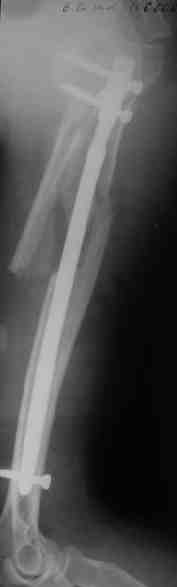

Уважаемые коллеги.

Прооперировали больную с переломом плеча все же гвоздем, Фото в приложении.

Re: Оскольчатый перелом плеча

Отправитель: Никита Заднепровский 20 Август 2006, 22:38

Интересно, а канал рассверливали?

Гвоздик похоже ЦИТОвский?

Полагаю, бабушку можно поздравить с обретением

независимости. Судя по снимкам, неврологических расстройств нет и такая пациентка выпишется после снятия швов.

Какие рекомендации Вы дадите этой женщине на ближайшие 6 месяцев?

Отправитель: Maxim Agalakov 20 Август 2006, 22:42

> Интересно, а канал рассверливали?

минимально

> Гвоздик похоже ЦИТОвский?

точно

> Какие рекомендации Вы дадите этой женщине на ближайшие 6 месяцев?

ЛФК, ну и гиревым спортом не заниматься:)

Отправитель: Alexaander Chelnokov 20 Август 2006, 23:36

|

Немножко уточню ответы Максима.

НЗ> Интересно, а канал рассверливали?

Только сформировали канал в головке. Диафиз не рассверливали. Хотя при необходимости, конечно, рассверлили бы.

НЗ> Гвоздик похоже ЦИТОвский?

Гвоздь большеберцовый нашей модификации, действительно, их делает предпричятие "ЦИТО". Тут взят 9 мм, укорочен до 240 мм, сделано дополнительное отверстие самое проксимальное, ну и для дистального винта.

НЗ> независимости. Судя по снимкам, неврологических расстройств

НЗ> нет и такая пациентка выпишется после снятия швов.

Неврологии нет, а выписать можно хоть на второй день, швы можно снять и в местной больнице.

НЗ> Какие рекомендации Вы дадите этой женщине на ближайшие 6 месяцев?

Почему так надолго? На ближэайшие недели - разработка движений, и все. Полагаю, что недель после 4 никаких рекомендаций не будет нужно, просто жить обычной жизнью сельской пенсионерки.